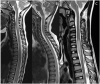

Relapsing demyelinating syndromes (RDS) in children encompass a diverse spectrum of entities including multiple sclerosis (MS) acute disseminated encephalomyelitis (ADEM), aquaporin-4 antibody associated neuromyelitis optica spectrum disorder (AQP4-NMOSD) and myelin oligodendrocyte glycoprotein antibody disease (MOG-AD). In addition to these, there are "antibody-negative" demyelinating syndromes which are yet to be fully characterized and defined. The paucity of specific biomarkers and overlap in clinical presentations makes the distinction between these disease entities difficult at initial presentation and, as such, there is a heavy reliance on magnetic resonance imaging (MRI) findings to satisfy the criteria for treatment initiation and optimization. Misdiagnosis is not uncommon and is usually related to the inaccurate application of criteria or failure to identify potential clinical and radiological mimics. It is also notable that there are instances where AQP4 and MOG antibody testing may be falsely negative during initial clinical episodes, further complicating the issue. This article illustrates the typical clinico-radiological phenotypes associated with the known pediatric RDS at presentation and describes the neuroimaging mimics of these using a pattern-based approach in the brain, optic nerves, and spinal cord. Practical guidance on key distinguishing features in the form of clinical and radiological red flags are incorporated. A subsection on clinical mimics with characteristic imaging patterns that assist in establishing alternative diagnoses is also included.